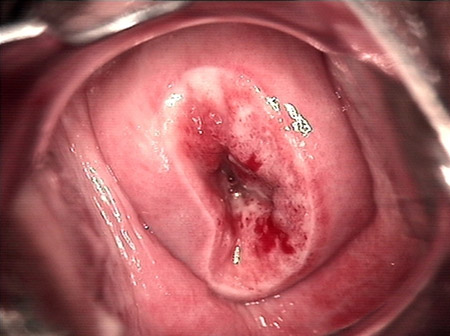

婦科leep錐切手術 CIN2-3

• CIN 2-3 leep術后CIN 2-3 leep術后